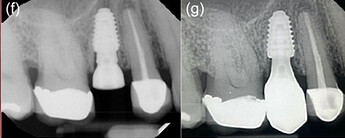

Minimally invasive removal of fractured central incisor and placement of immediate implant (Megagen Anyridge) without osteotomy on Patient 1: (a) Immediate prepless immediate implant on central incisor. (b) Anatomical healing abutment placed. (c) Transmucosal tunnel and emergence profile development by anatomical healing abutment. (d) Peri‐apical radiograph on the day of implant placement with anatomic healing abutment. (e) Peri‐apical radiograph with final restoration at 12 months. (f) Definitive monolithic Zr restoration.